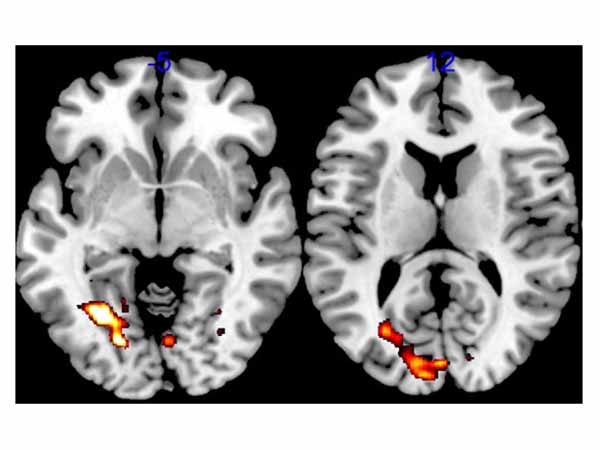

- Electrophysiological biomarker of memory for Alzheimer's disease

- Brain network dynamic during short-term memory binding: a study across the lifespan